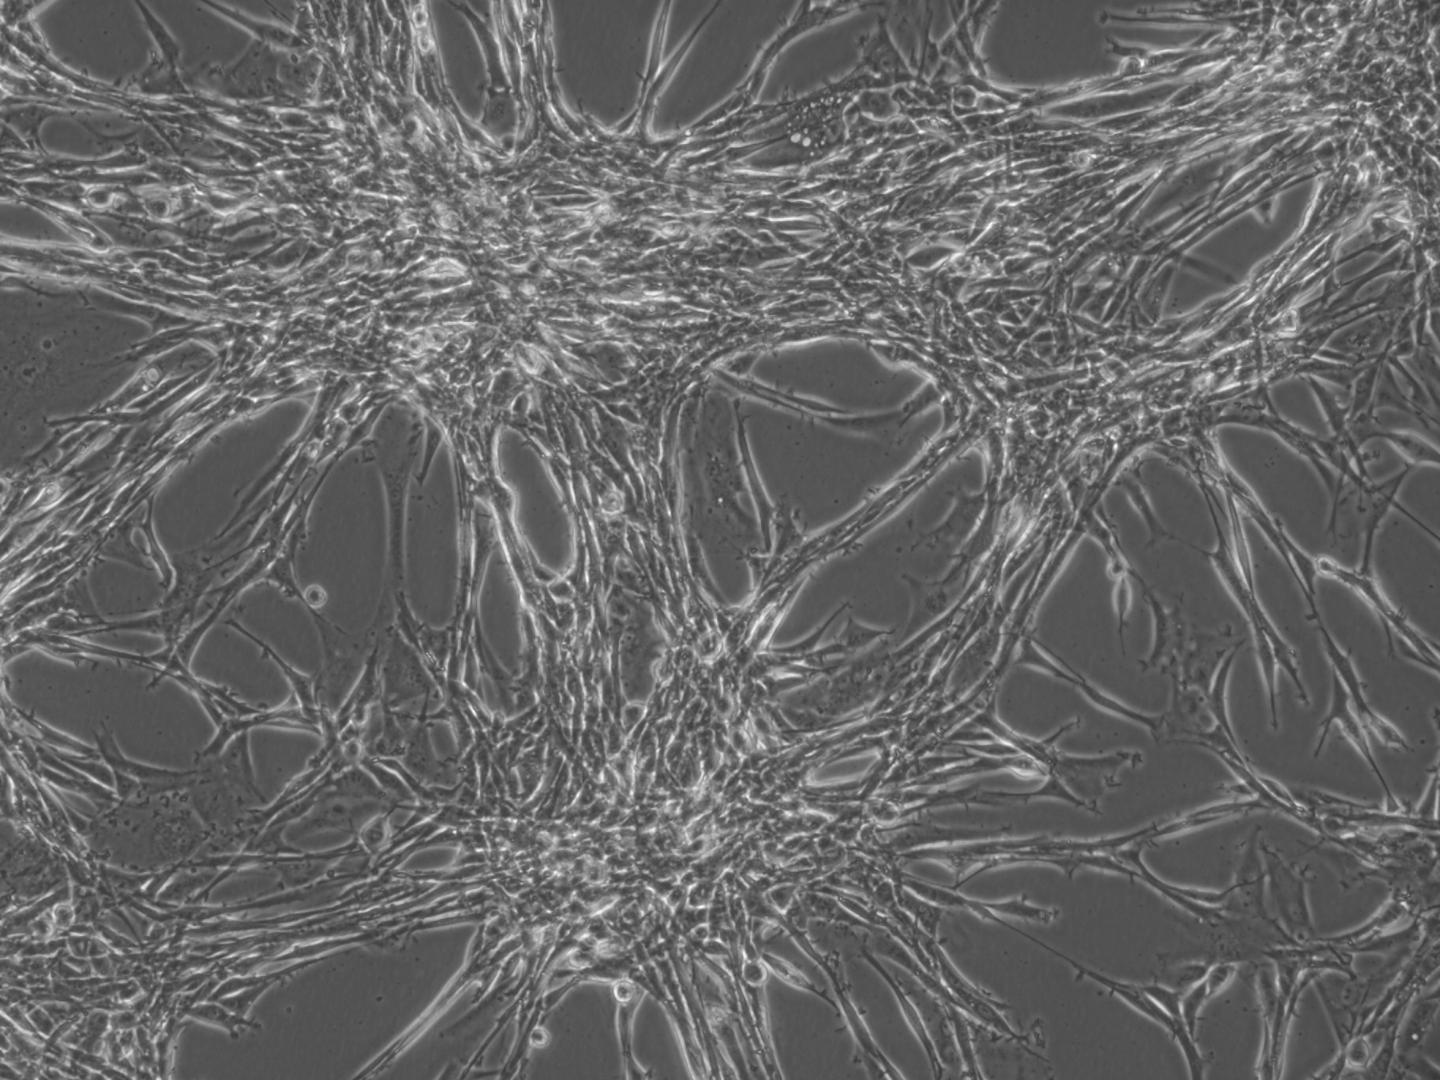

Glioblastoma Multiforme (GBM) cells in culture (Photo: Jin-Min Nam)

Jin-Min Nam